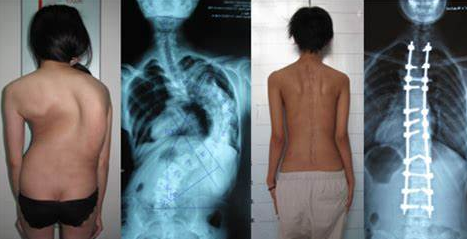

脊柱侧弯对青少年的危害很大,不仅影响外观。还可能影响心、肺功能的正常发育生长,以及青少年的身心健康。如果严重的话会引起身体各大系统功能均受不同程度的影响。

由于脊柱侧弯,影响了人体骨骼的正常生长发育,导致脊柱变形、肩背部不平、胸廓畸形、驼背、鸡胸、肩不等高、背不等平、骨盆倾斜、腿不等长,身体扭曲,身躯矮小。因为外形的异常,患者会产生自卑心理,不喜欢和人交往,久而久之会影响心理的健康,严重的会发展成自闭症。

其次,根据病情严重程度,制定个性化治疗方案,根据病情选择保守治疗或者手术治疗,具体请遵医嘱。我院骨科团队有专业的脊柱外科专家坐诊,目前已开展脊柱侧弯矫形治疗,可为广大青少年提供专业筛查、个性化治疗等优质高效的医疗保障。

(图片来源于网络,感谢原作者,如有侵权,联系作者删除)